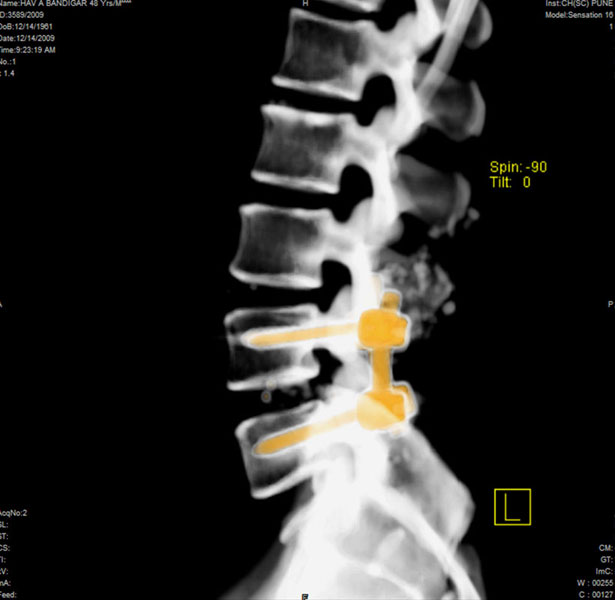

Spondylolisthesis malformations

Spondylolisthesis implies slippage of one lumbar vertebra over the next one, causing pain and nerve compression. Patient can also have difficulty in walking and numbness of the legs. Usually these patients need evaluation lumbar spine by MRI and CT scan, followed by spinal instrumentation and fusion.